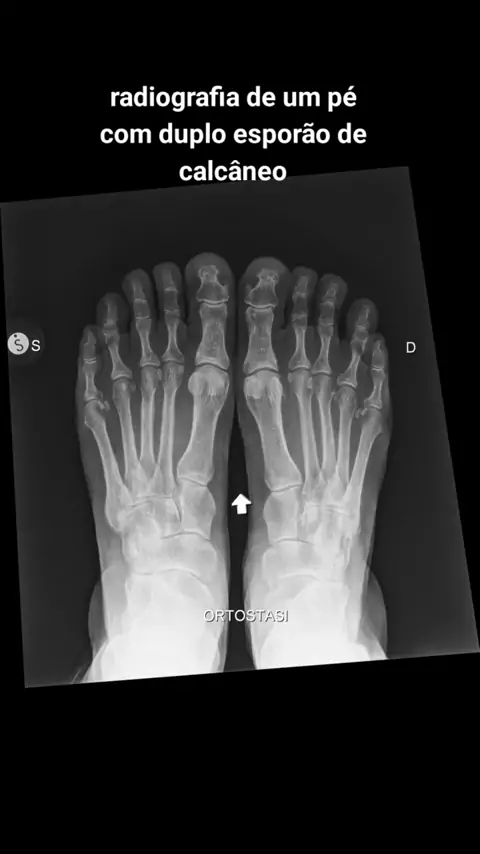

toda a beleza de uma radiografia #medicina #viral #fy #video